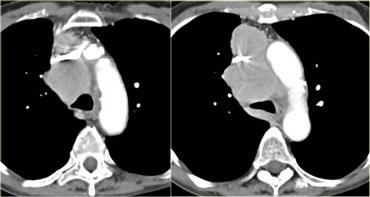

Hãy mô tả hình ảnh bên trái.

Sau đó tiếp tục.

Có nhiều khối ở cả trung thất trước và trung thất giữa.

Giá trị tỷ trọng tương đương tỷ trọng nước.

Các dấu hiệu này gợi ý chẩn đoán hạch bạch huyết dạng nang ở bệnh nhân có bệnh lý di căn.

Có một tổn thương dạng nang ở trung thất giữa.

Có mức dịch-dịch với hình ảnh sữa canxi (milk of calcium).

Nang đường ruột nguyên thủy đôi khi có thể chứa sữa canxi như trong ví dụ này về nang đôi thực quản.